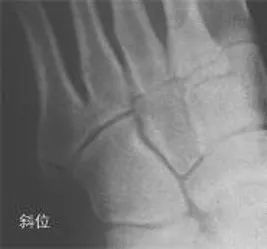

在足正位X线上,第1、2、3跖骨的内外侧缘分别和它相对应的楔骨的内外侧缘呈一直线排列;第一、二跖骨基底间隙和内中楔骨间隙相等。

30°斜位上:1、第四跖骨内侧缘和骰骨内侧缘连续成一条直线2、第三跖骨内侧缘和外侧楔骨内侧缘连续成一条直线3、第二、三跖骨基底间隙和内、中楔骨间隙相等。

侧位上,跖骨不超过相应楔骨背侧缘。从远端的跖骨经过跖跗关节到近端的跗骨,应该是一条不间断的连线

2005年Pearse等提出“ABC”的方法来阅读足部X 线片, 以减少中、前足的漏诊。 A ( alignment)检查跖骨与相应楔骨的对应线 B ( bone)检查每一块骨的轮廓 C ( congruity )检查整体一致吻合, 在正位片上观察内柱, 在斜位片上观察中、外柱。侧位片的常规检查可发现Lisfranc关节矢状面的半脱位及撕脱性骨折

特殊放射学检查应力位摄片:评价跖跗关节的稳定性负重位摄片:评价足的纵弓的稳定性,以及明确第1跖骨间隙的增宽 外侧斜位:诊断细微的第1跖骨间隙的增宽CT 扫描:诊断不明显的跖跗关节半脱位对照位摄片:明确细微的损伤